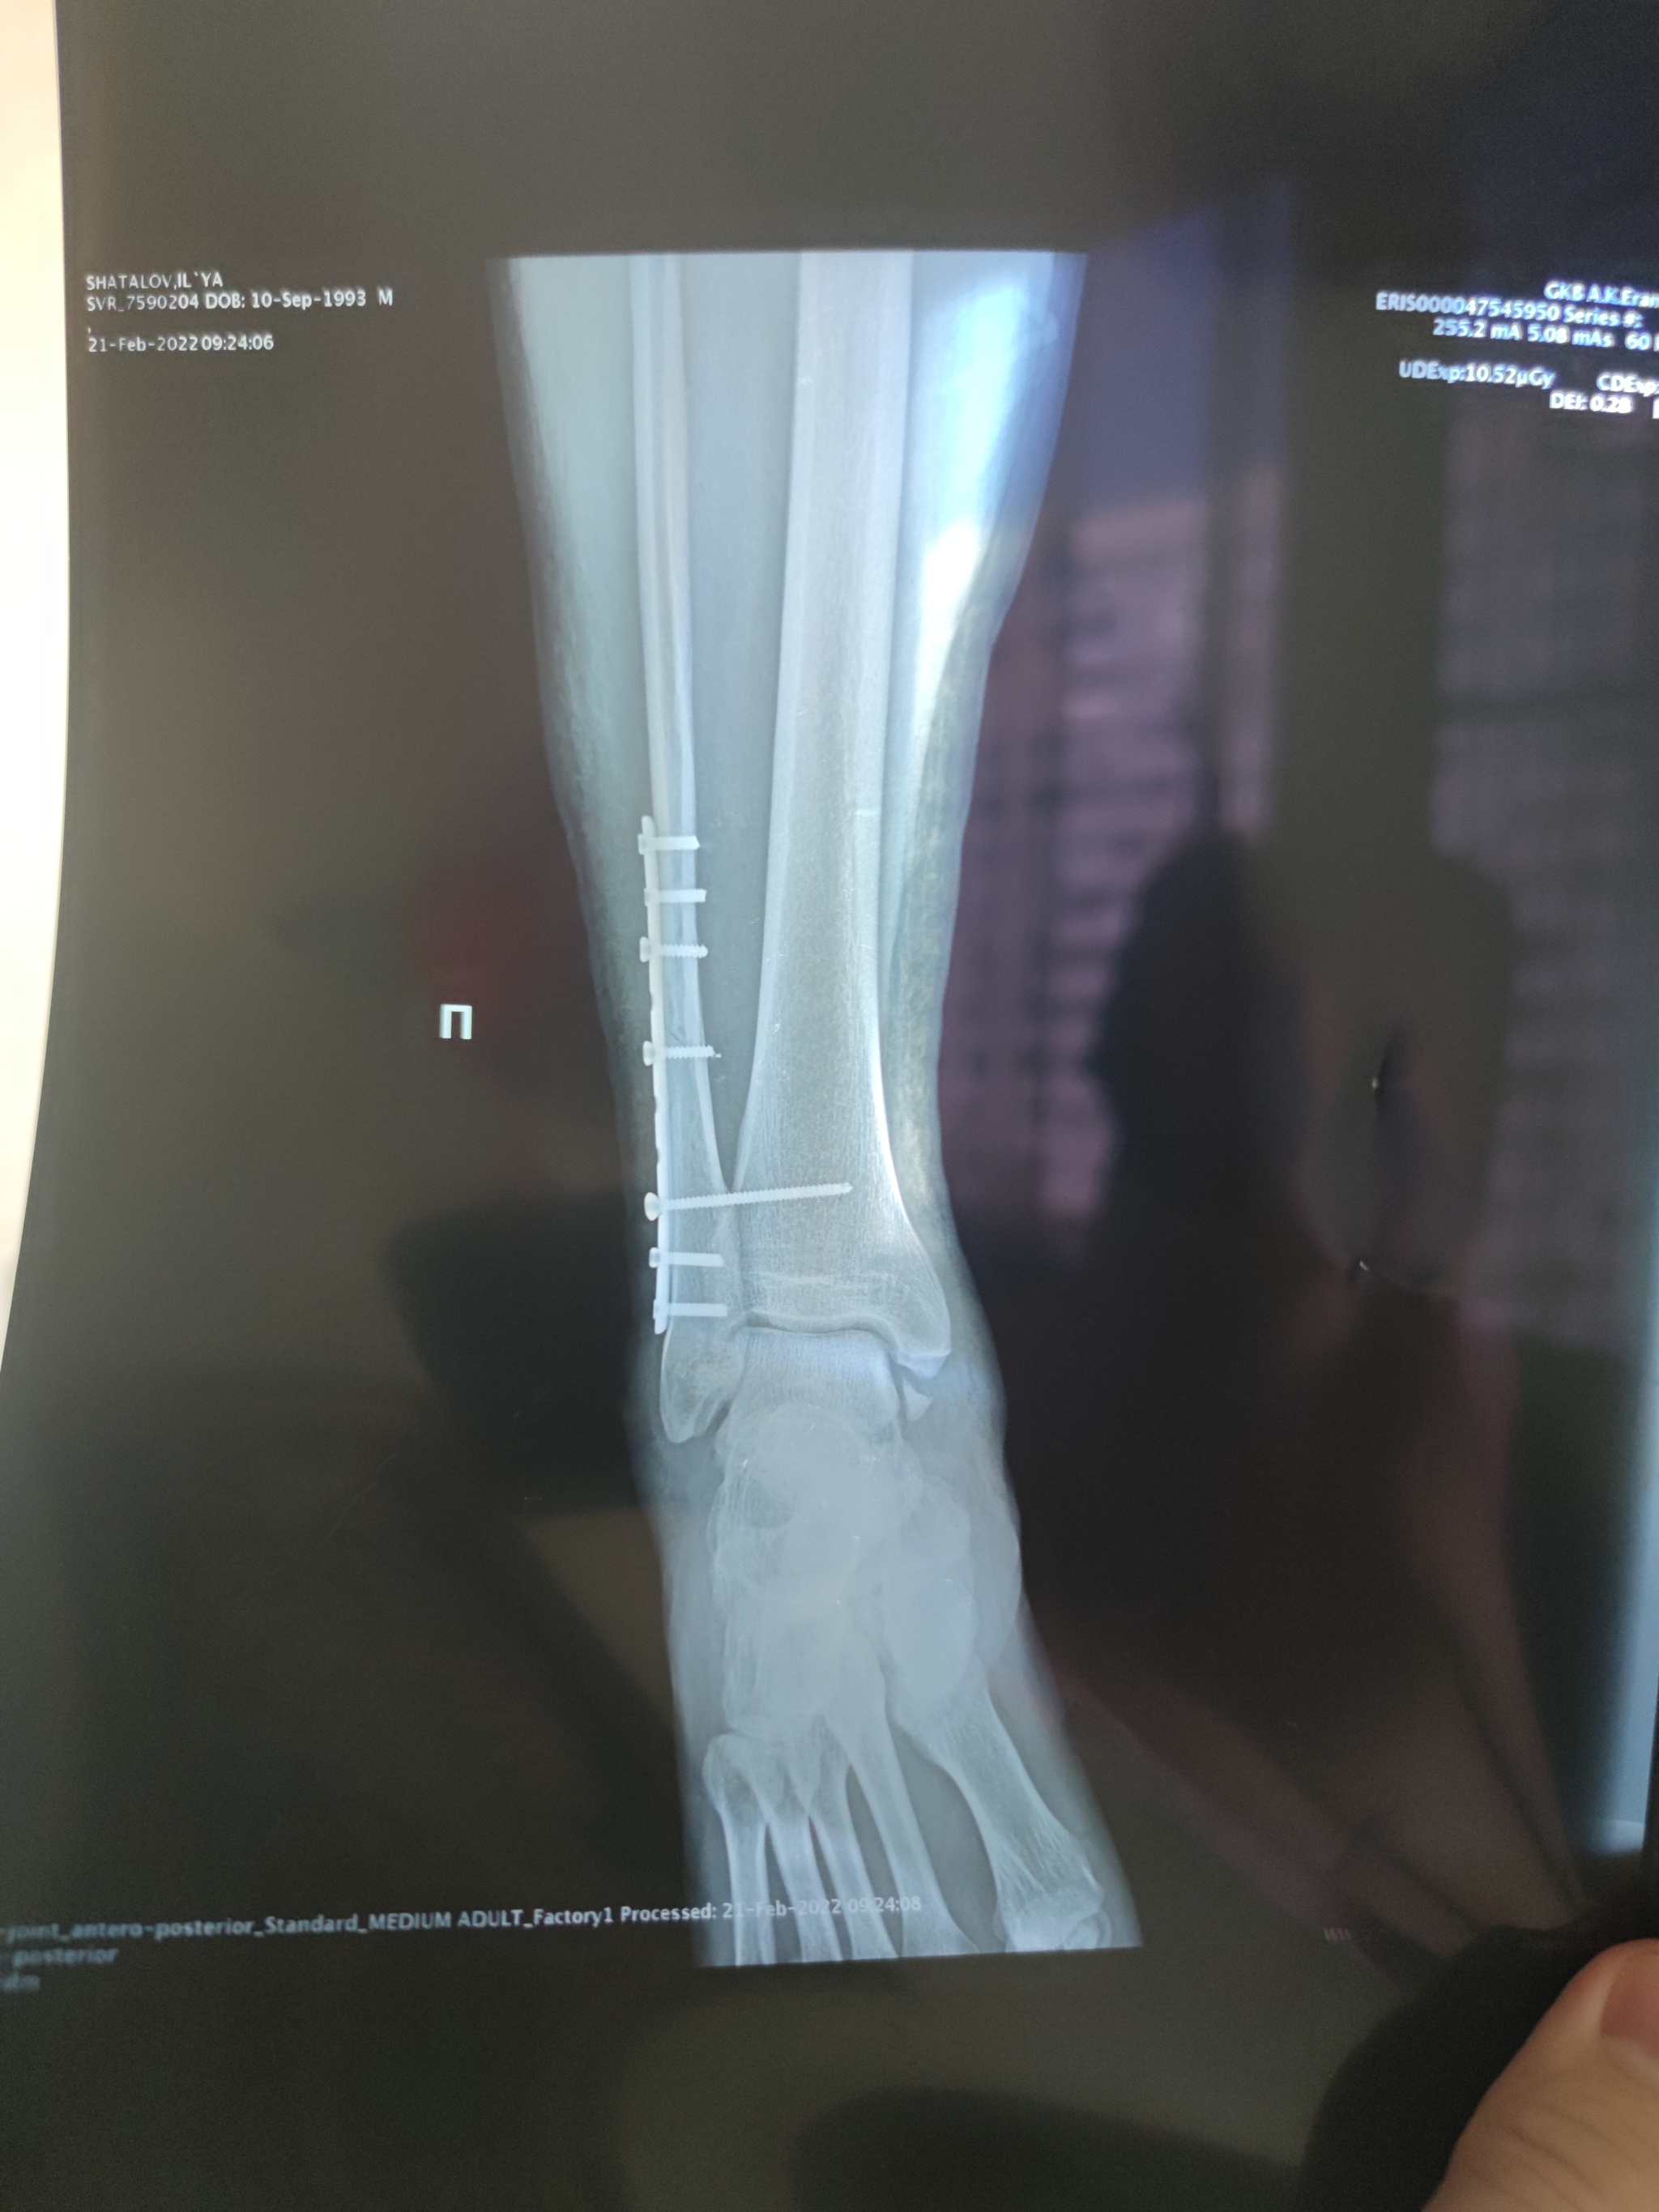

19 февраля этого года сломал ногу. Трехлодыжечный перелом+ остиосинтез(установка металла в ногу).